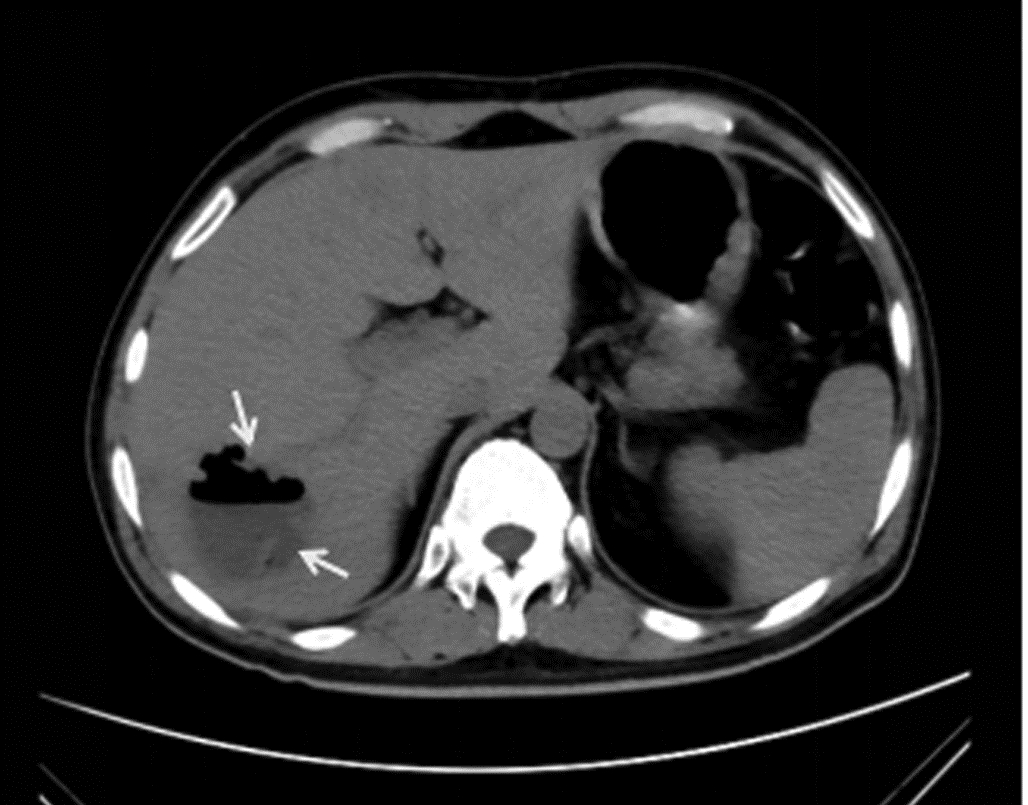

2型糖尿病合并肝脓肿继发脑脓肿1例报告

2022, 38(6): 1375-1376. DOI: 10.3969/j.issn.1001-5256.2022.06.031

摘要: